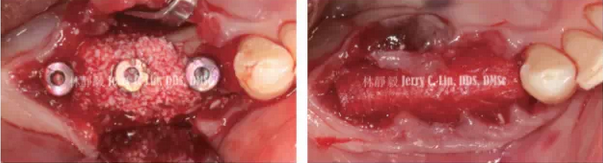

嚴(yán)重種植體周圍炎的處理(二)——林靜毅醫(yī)師